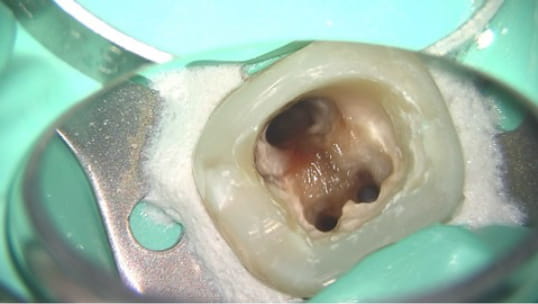

治療中に歯の中に唾液が入ってしまったり、滅菌・消毒されてない器具で歯の中を触ったりすると、

治療しているにも関わらず、逆に病気を作り出しています。

治療の最初から最後まで細菌が入らない環境にしてはじめて精密な治療が意味あるものになります。

当院ではラバーダム使用など、エビデンスに基づいた万全の細菌感染対策を行って治療を行っております。

根管の中を洗浄し、無菌に近い空の状態にした。

根管の中を封鎖し終了。

根管の中が無菌に近い状態になるように洗浄を繰り返します。

根管の中を封鎖し、根管治療終了